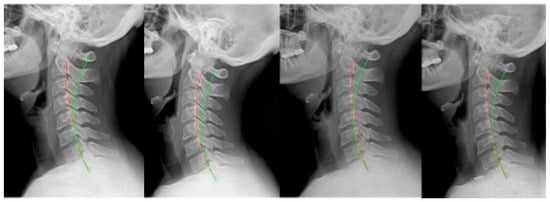

2. Materials and Methods

3. Results

| Pre- rehab | ARA | −12.5° | −0.7° | −11.7° | −23.0° | −14.8° | −5.9° | −23.7° | −13.2° (8.4°) |

| TzH | 13.6 mm | 21.6 mm | 17.2 mm | 18.6 mm | 35.6 mm | 23.3 mm | 20.6 mm | 21.5 mm (7.0 mm) | |

| APL | −13.9° | −14.4° | −25.6° | −17.7° | −17.6° | −14.1° | −21.4° | −17.8° (4.4°) | |

| Post- rehab | ARA | −37.6° | −26.3° | −36.0° | −36.6° | −35.4° | −31.7° | −29.8° | −33.3° (4.2°) |

| TzH | 8.1 mm | 18.3 mm | 1.9 mm | 9.2 mm | 16.6 mm | 17.2 mm | 12 mm | 11.9 mm (6.0 mm) | |

| APL | −23.9° | −27.3° | −34.0° | −28.3° | −28.4° | −25.7° | −25.1° | −27.5° (3.3°) | |